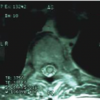

38

A 65-year-old man is evaluated because of a slowly progressive, nine-month history of urinary dysfunction, midthoracic pain, and difficulty walking. Physical examination shows inability to tandem walk, a T8 sensory level, and weakness in the lower extremities graded at 4/5. The T2- weighted axial MR image of the thoracic spine at the T6 level shown is most consistent with which of the following? Answers: A. Type 4 Spinal Vascular Malformation B. Type 2 Spinal Vascular Malformation C. Spinal cord infarction D. Type 1 Spinal Vascular Malformation E. Type 3 Spinal Vascular Malformation

Correct Answer: Type 1 Spinal Vascular Malformation